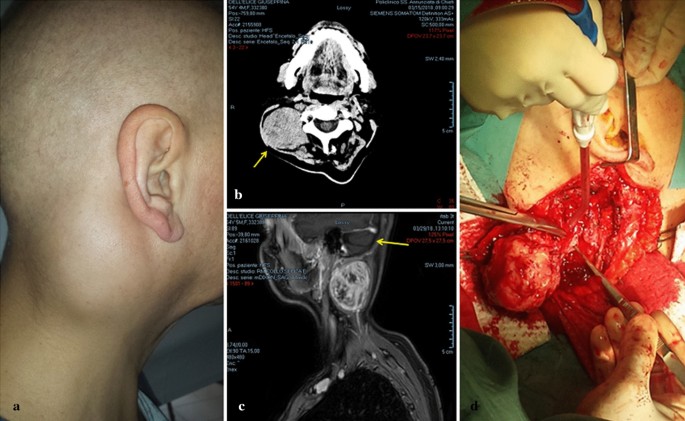

A multiparous 54-year-old woman presented to the department of otolaryngology in February 2018 with a round mass, approximately 5 cm in diameter, in the posterior triangle of the right side of the neck (Fig. 1a). The mass was firm, fixed, and painful on palpation. For the past 6 months she had been suffering from neck pain, which was interpreted as torticollis and treated with analgesics without relief. Whole-body contrast-enhanced computed tomography (CT) scan revealed a solid 5.5 × 4.5 cm mass in the right posterior neck region near C1 and C2, without bone infiltration or enlargement of the carotid space lymph nodes (Fig. 1b); there was also a 0.8-cm subcutaneous nodule near the anterolateral arch of the right third rib and the axillary cavity. The lungs and liver were normal. Contrast-enhanced magnetic resonance imaging (MRI) of the neck showed a heterogeneously hyperintense mass displacing the paravertebral muscles, and a distinct cleavage plane between the mass and the sternocleidomastoid muscle (Fig. 1c). Fine needle aspiration cytology (FNAC) was performed twice, however, only few lymphoid cells and erythrocytes were observed.

Representative preoperative, CT scan, MRI, and surgical excision images. a Preoperative photograph of the mass in the right posterior neck region. b CT scan showing a solid mass (indicated by the arrow) in the posterior neck region near C1-C2. c MRI image showing a hyper-intense mass displacing paravertebral muscles (arrow), and a cleavage plane between the mass and the sternocleidomastoid muscle. d Surgical excision of the mass by posterior neck cervicotomy